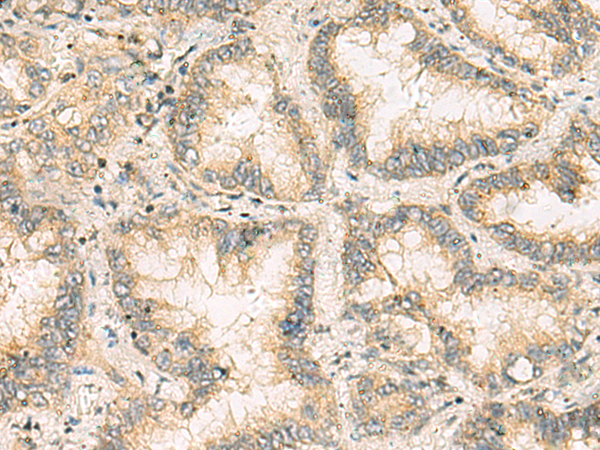

分类: 科研抗体货号: P10314别名: p23; TMP21; p24d1; S31I125; Tmp-21-I; S31III125; P24(DELTA)应用: WB,IHC反应种属: Human, Mouse, Rat